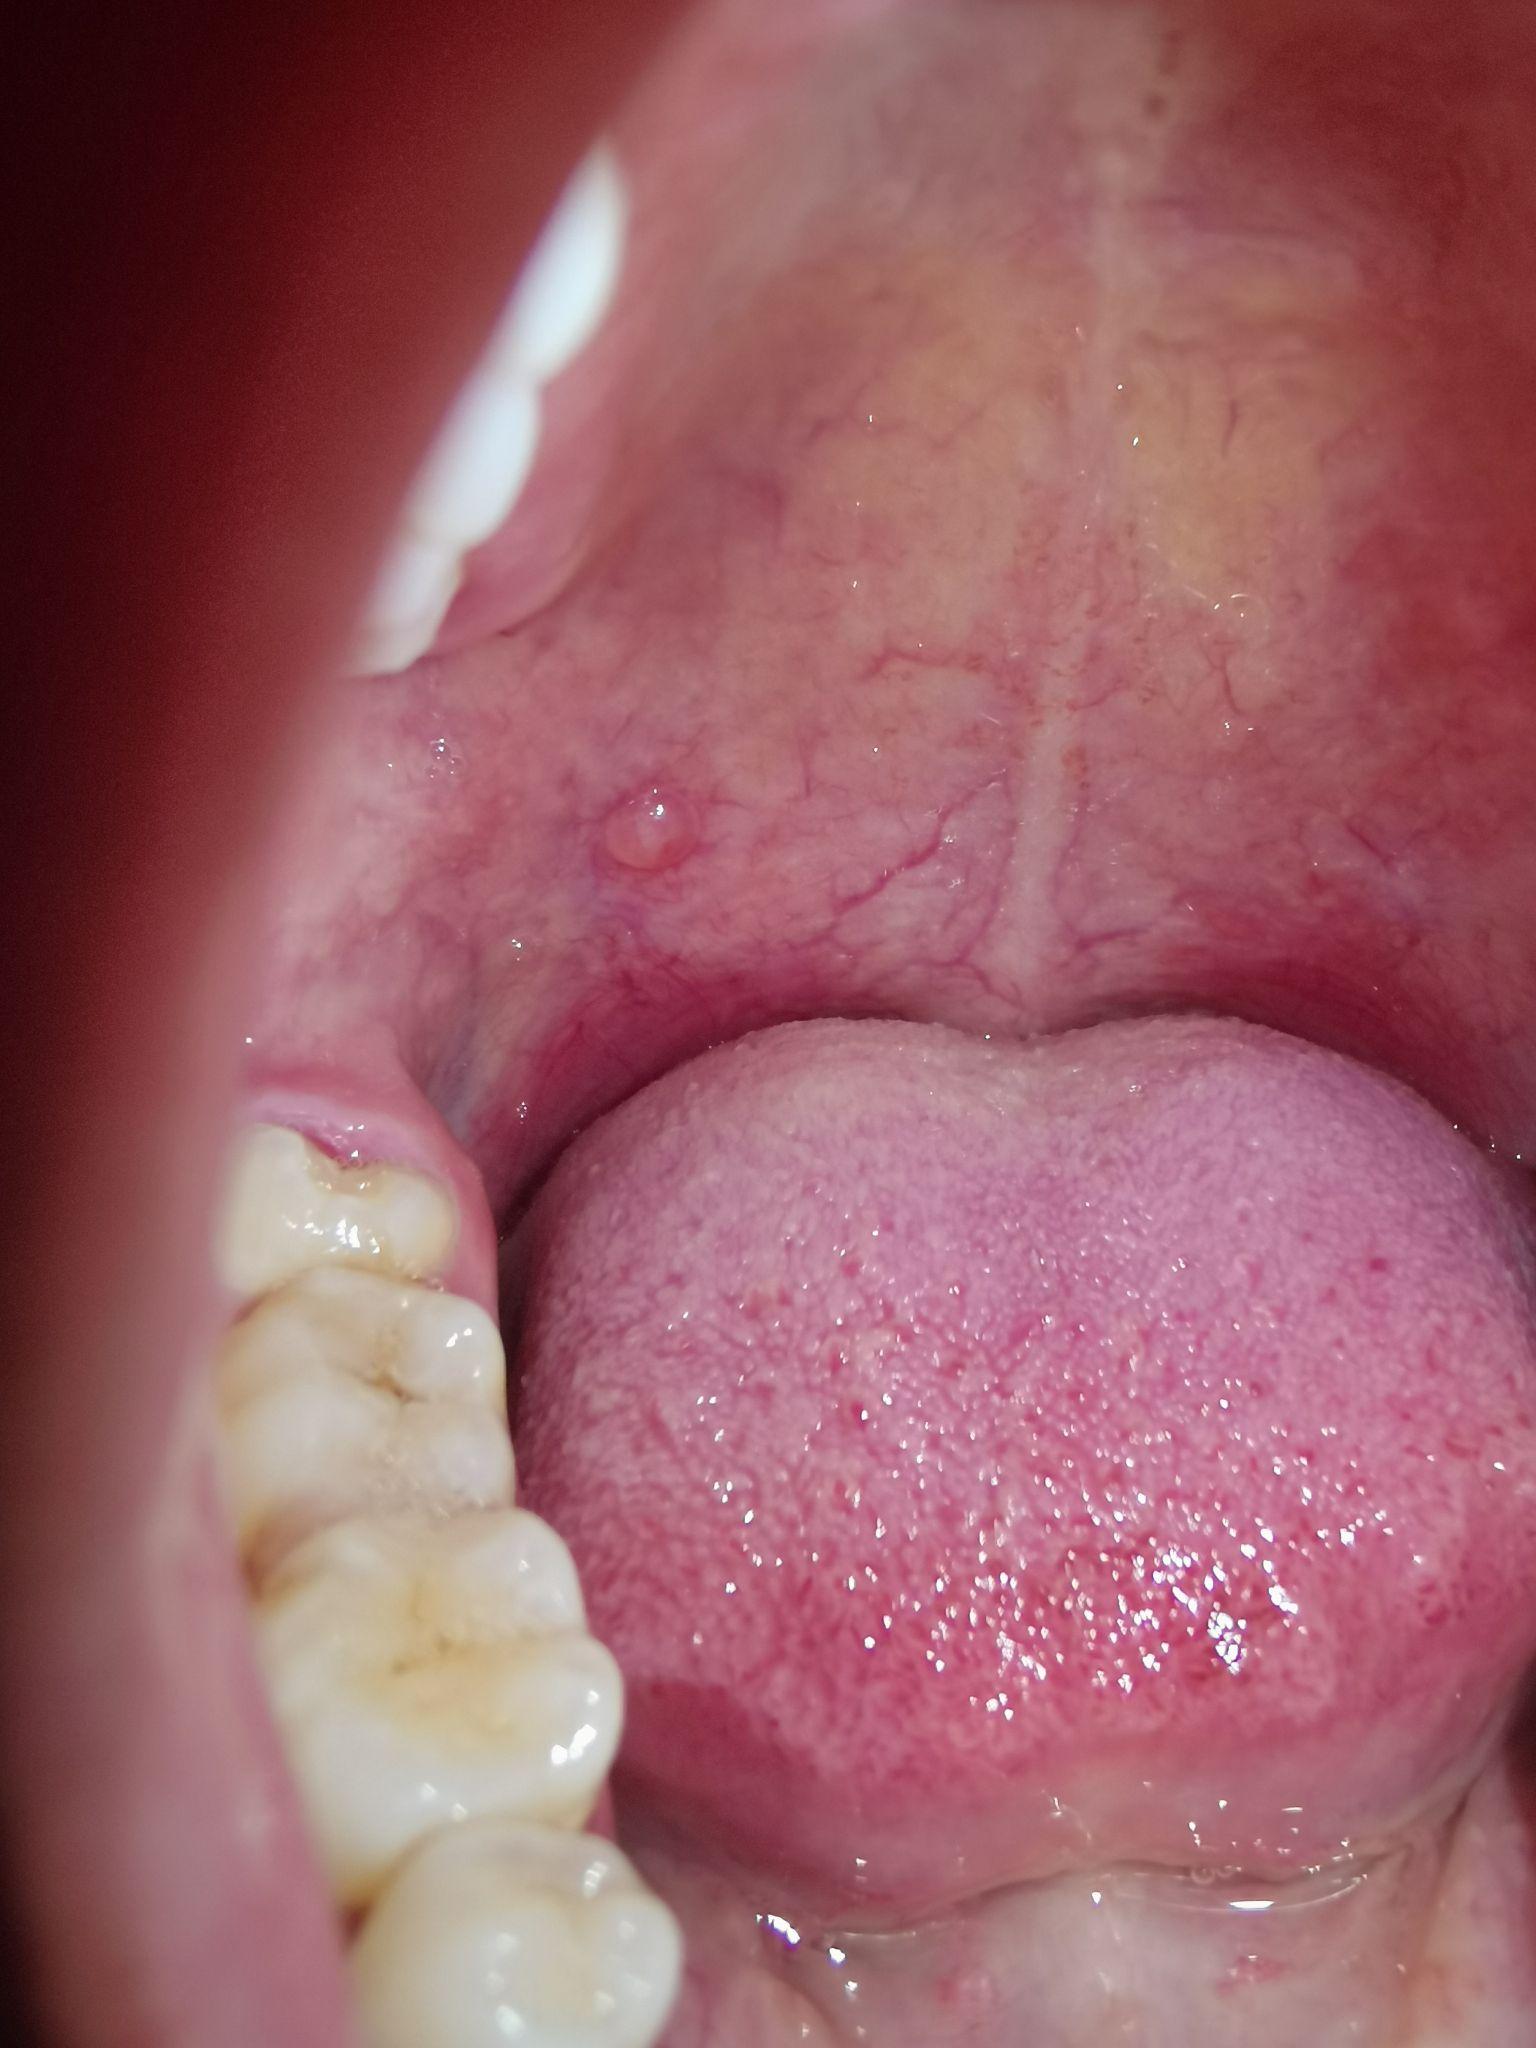

上颚长了一个疙瘩,不会痛,也不影响吃饭那些,请问这是口腔癌前病变吗?

图片尺寸450x600